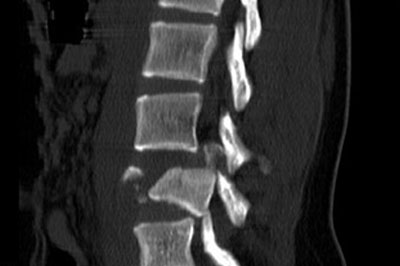

Disc prolapse

disc-prolapse

Disc is a cushion like strecture lying between the vertebral bones.Jelly like substance within the disc is responsible for the flexibility of back bone...

Disc is a cushion like strecture lying between the vertebral bones. Jelly like substance within the disc(Nucleus pulposus) is responsible for the flexibility of back bone. Some times the jelly like substance comes out of its boundary and is called as disc prolapse .

disc-prolapse-intro

Disc prolapse if occurs in the neck it causes neck pain with arm pain. If it occurs in low back it causes lowback pain with leg pain.Pt might also have weakness and numbness of arm or leg depending upon the severity of nerve compression.

Xray is the first investigation needed. MRI may be needed if pain or weakness is severe.

Mostly pain will subside with physiotherapy , rest and pain medications. Discectomy surgery might be needed if pt has persistent arm or leg .